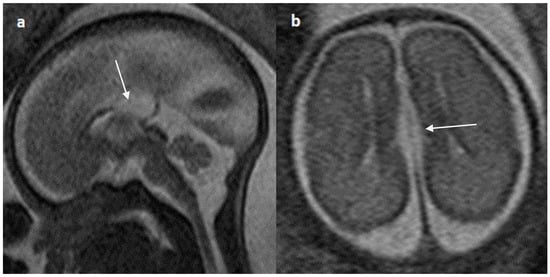

Figure 7.

Fetal MRI images of a 20 gestational weeks aged fetus with complete agenesis of the corpus callosum. (a) A T2-weighted sequence image in axial plane showing non-decussating anterior-posterior white matter tracts known as Probst bundles medial to the lateral ventricles (arrow). (b) A T2- weighted sequence coronal image showing Probst bundles indenting superomedial margins of lateral ventricles. Probst bundles are seen with complete agenesis of the corpus callosum.